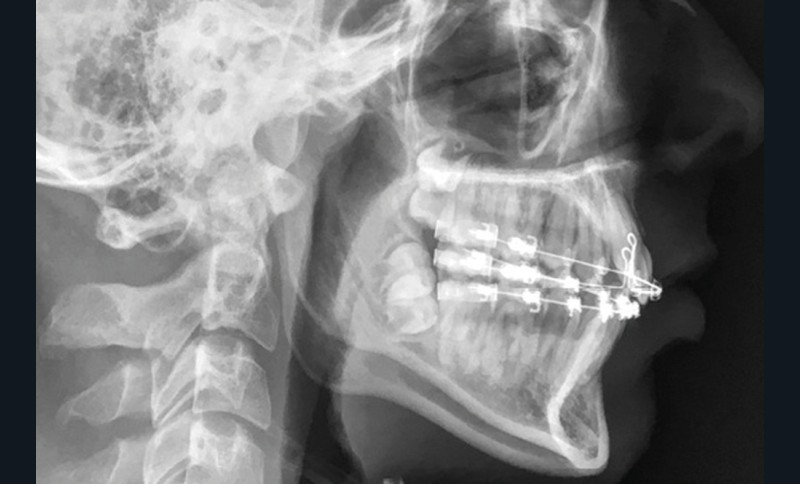

L’analyse de la téléradiographie de profil (fig. 1g) confirme une classe II squelettique à tendance hyperdivergente avec une normo-position de l’incisive mandibulaire dans sa symphyse. L’âge du patient et la croissance mandibulaire en rotation postérieure (travaux de Björk) ne permettront sans doute pas une correction de la classe II squelettique sans version de l’incisive mandibulaire.

La comparaison des téléradiographies de profil et l’analyse de la superposition générale sur les structures stables basi-crâniennes (fig. 7) montrent une absence de croissance antéro- postérieure (pas de changement de l’angle ANB) mais une ouverture du sens vertical (angle FMA passant de 24° à 26°) qui reste sans conséquences esthétiques. L’incisive mandibulaire est repositionnée (angle IMPA passant de 99° à 97°). La rotation horaire du plan palatin, de même que l’égression de l’incisive maxillaire, correspond à l’action des tractions intermaxillaires de classe II.